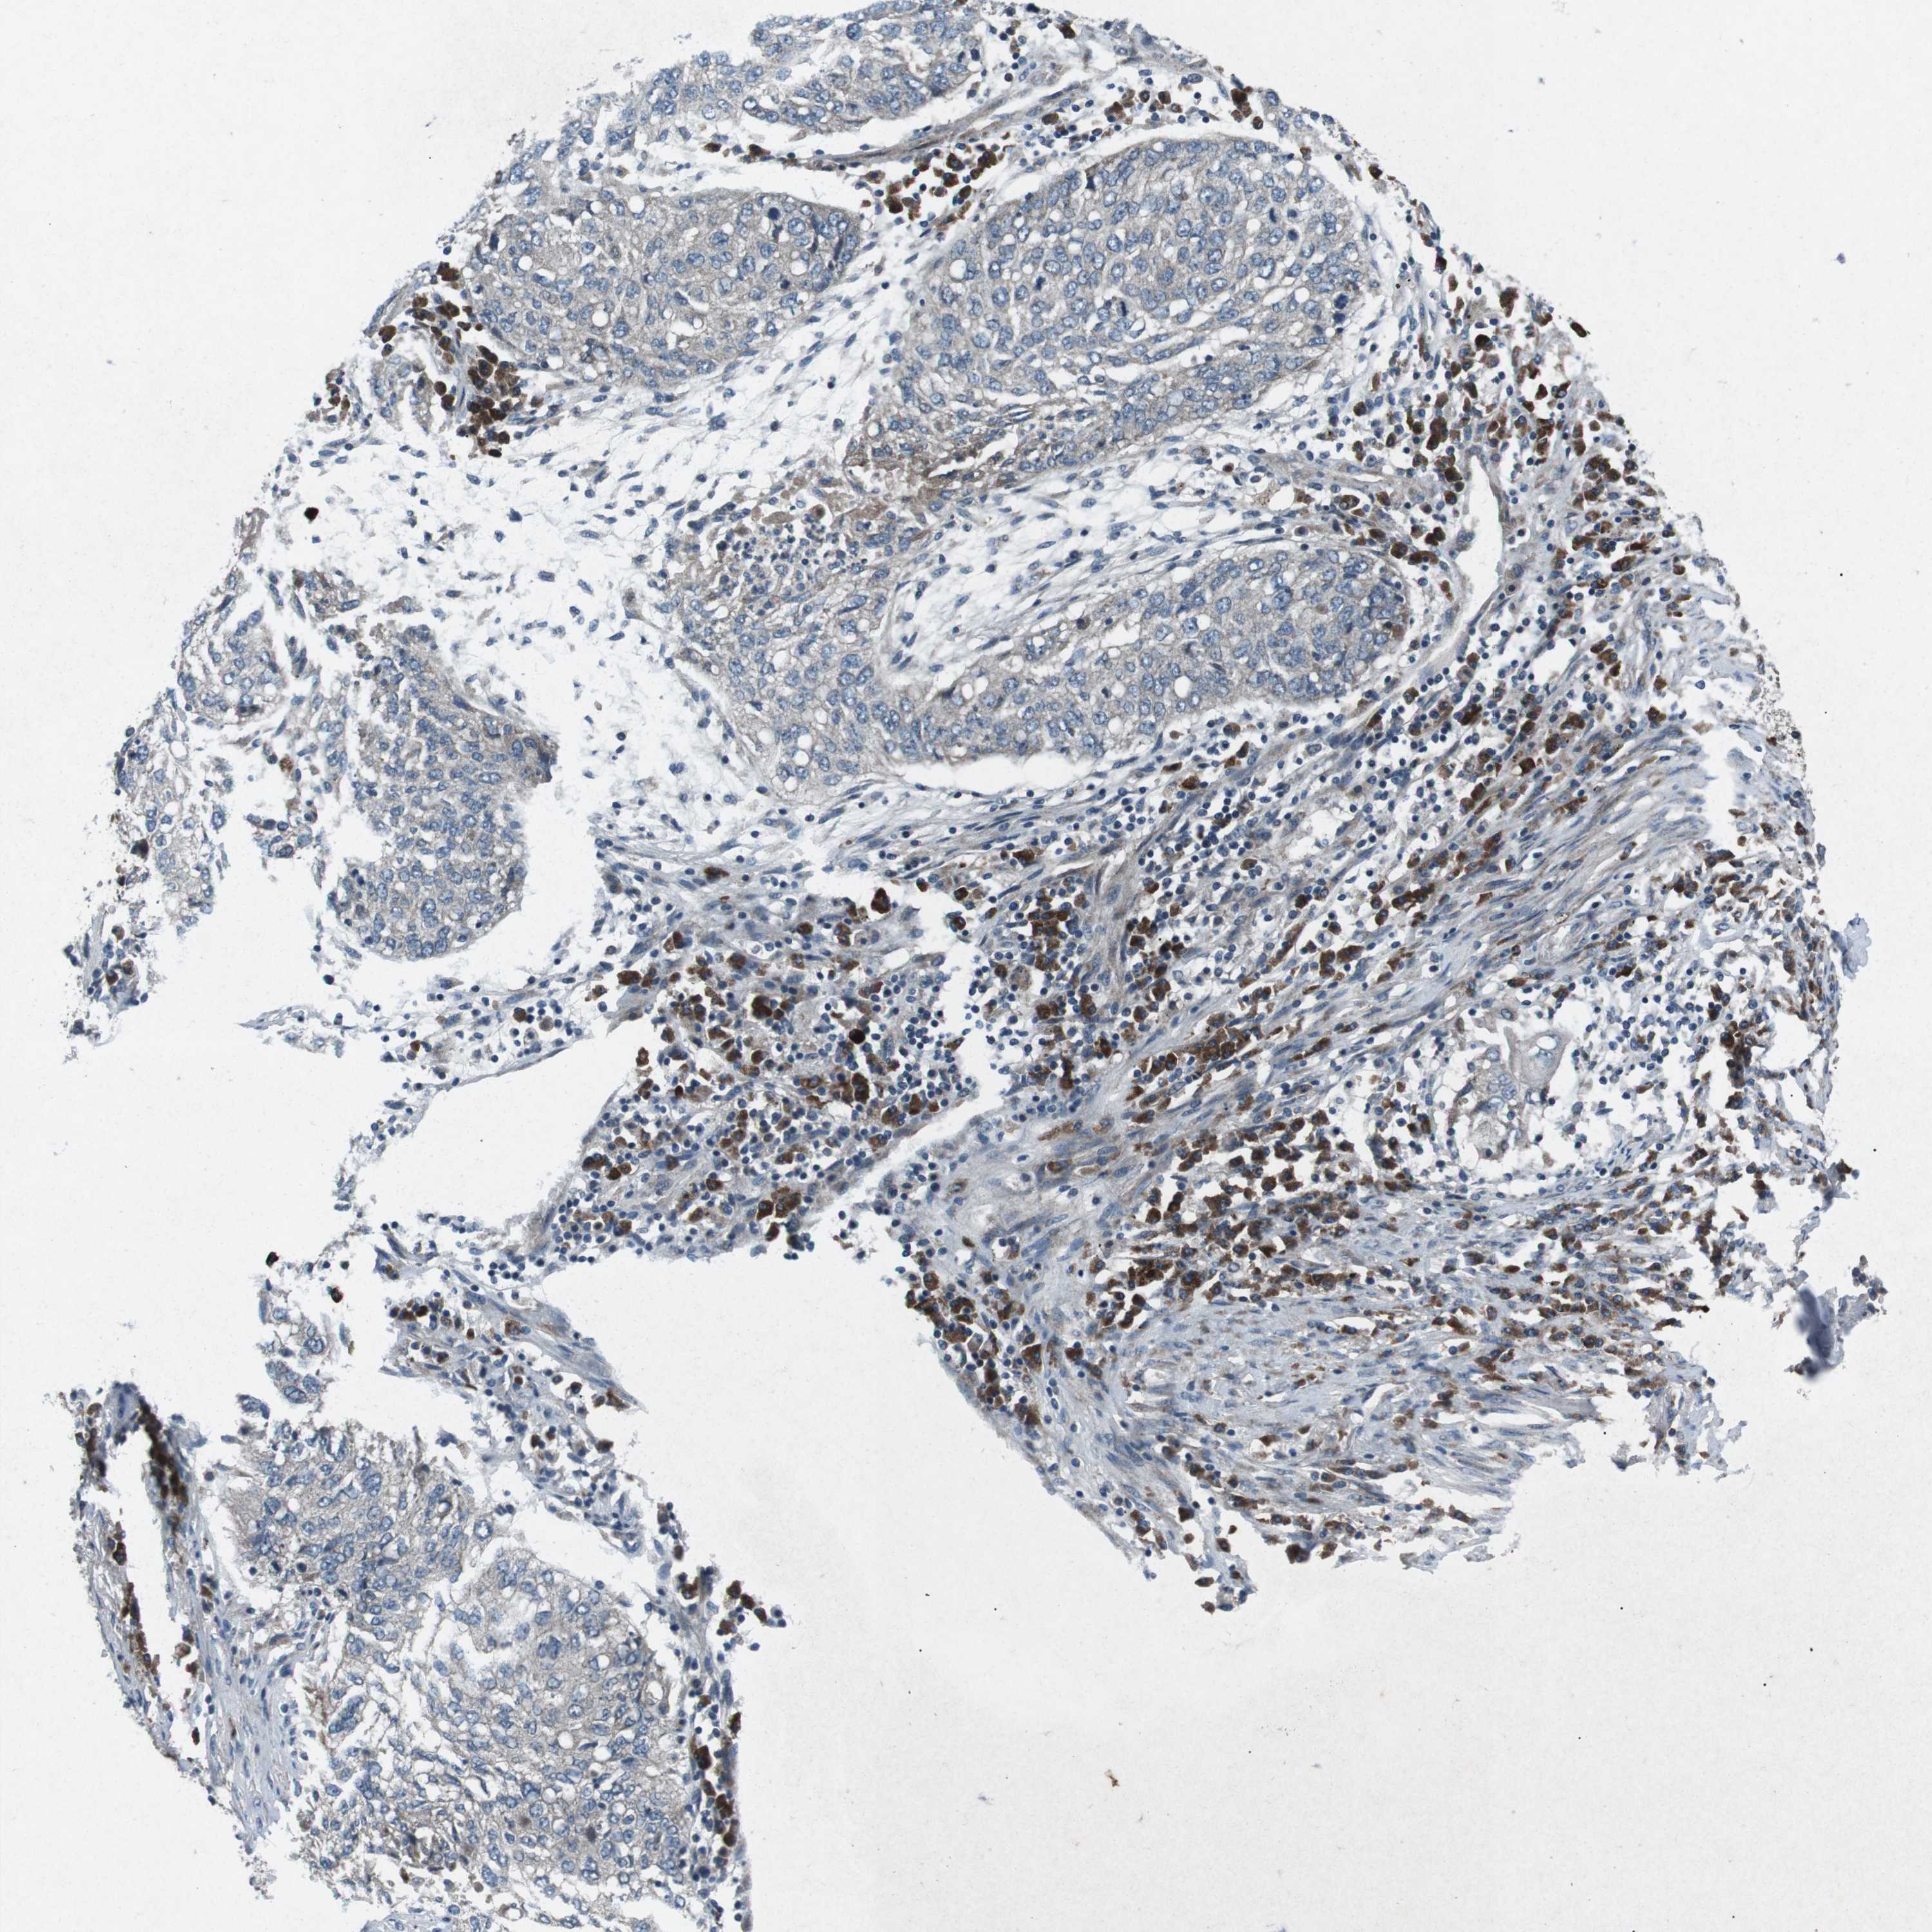

CDK16 is potential prognostic, high expression is unfavorable in Lung Adenocarcinoma (validation)

Best expression cut offi

Based on the FPKM value of each gene, patients were classified into two groups and association between prognosis (survival) and gene expression (FPKM) was examined. The best expression cut-off refers the FPKM value that yields maximal difference with regard to survival between the two groups at the lowest log-rank P-value. Best expression cut-off was selected based on survival analysis .

When clicking on this number, the vertical dashed line indicating cut-off, the interactive survival plot, and the Kaplan-Meier curve will be adjusted to show results based on the best expression cut-off.

: 62.91

P scorei

Log-rank P value for Kaplan-Meier plot showing results from analysis of correlation between mRNA expression level and patient survival.

N/A

5-year survival highi

5-year survival for patients with higher expression than the expression cutoff.

For melanoma and glioma, 3-year survival is shown.

5-year survival lowi

5-year survival for patients with lower expression than the expression cutoff.

Average pTPM 55.0

Number of samples 105